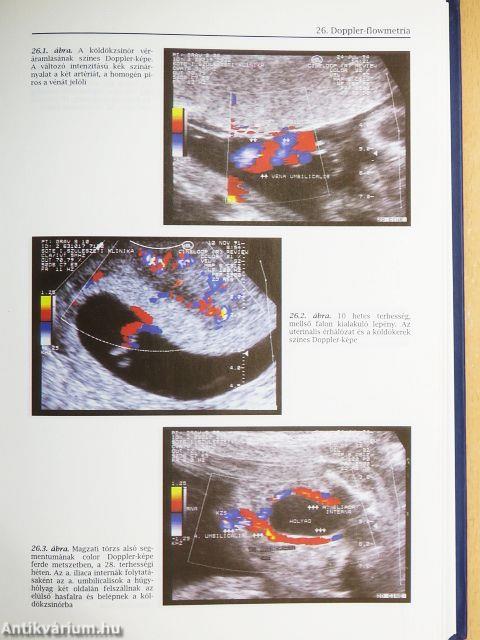

| Doppler-flowmetria (Szabó István és Papp Zoltán) | 277 |